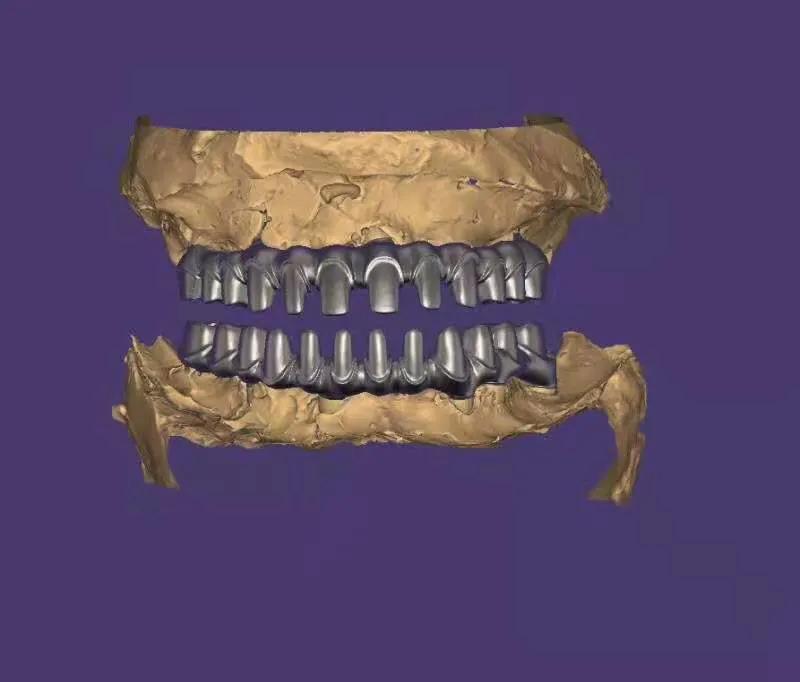

典型的負(fù)重,All-On-4。

這就是傳說(shuō)中的當(dāng)天戴牙當(dāng)天吃飯,網(wǎng)上到處宣傳的就是這種種植方法。但是不是每一個(gè)人都能做這個(gè),All-on-4一般需要預(yù)約,醫(yī)生種植完畢,技師馬上開(kāi)始取模做牙,大概5小時(shí)左右就可以戴上臨時(shí)牙回家吃飯了,休息一兩天,正常吃飯是沒(méi)問(wèn)題的。